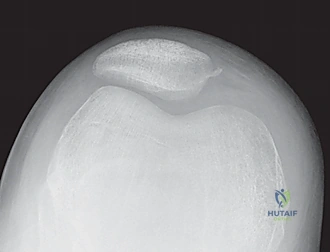

- Plain Radiographs:

- AP, Lateral, Sunrise/Merchant Views: Essential. The sunrise view, requiring 30-45 degrees of flexion, might be delayed due to acute pain but is crucial for assessing trochlear morphology and patellar tilt.

- Limitations: Plain films can miss up to 40% of arthroscopically documented chondral or osteochondral lesions. Subtle slivers of bone can be easily overlooked.

- MRI Scan: Highly recommended for all patients with a large traumatic effusion due to the high rate of occult articular or osteoarticular injury.

* Osteochondral Lesions: Crucial for determining size, location, and potential for repair versus removal.

* Bone Bruise Pattern: Confirms patellar dislocation (medial patella and lateral femoral condyle).

* Anatomical Risk Factors: Assesses patella alta, trochlear dysplasia, tibial tubercle-trochlear groove (TT-TG) distance.